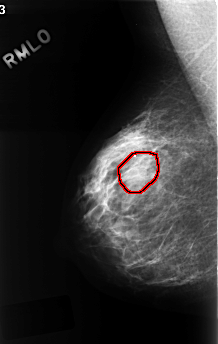

C_0330_1.RIGHT_MLO

FILE: C_0330_1.RIGHT_MLO.OVERLAY

TOTAL_ABNORMALITIES 1

ABNORMALITY 1

LESION_TYPE MASS SHAPE OVAL MARGINS OBSCURED

ASSESSMENT 3

SUBTLETY 1

PATHOLOGY BENIGN

TOTAL_OUTLINES 1

BOUNDARY